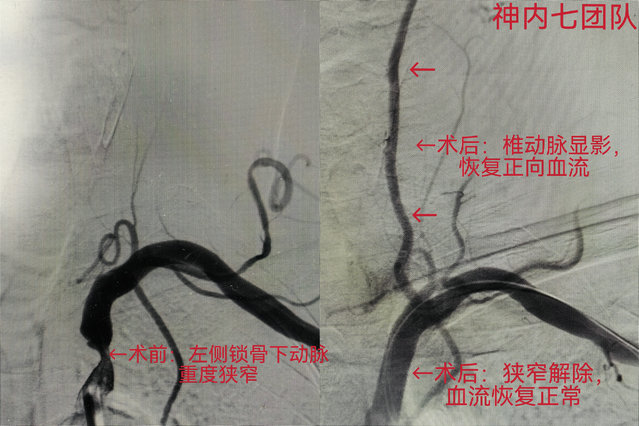

神经内七科副主任刘建鑫在详细询问病史后,没有简单依赖既有检查结果,而是为患者进行了细致的体格检查,正是这份“不放过任何细节”的职业敏感,让他在查体时敏锐地发现了一个异常信号:患者左手竟然触摸不到脉搏,且双侧上肢的收缩压压差明显大于正常范围。这一关键体征立即引起了团队的高度警惕,迅速为患者安排了血管超声及脑血管造影检查,最终明确诊断为—锁骨下动脉盗血综合征,这正是导致其脑部供血不足、症状反复的“罪魁祸首”,若不及时处理,未来发生脑梗死风险极高。

诊断明确后,神经内七科主任王丹、护士长殷蕾带领介入团队第一时间组织讨论,为患者量身制定了微创介入支架植入治疗方案。手术过程顺利,术后复查显示:孔先生狭窄的血管得到有效解除,血流通畅,原本异常的椎动脉血流方向也恢复了正向血流,困扰他已久的头晕、上肢无力等症状在术后即刻消失。